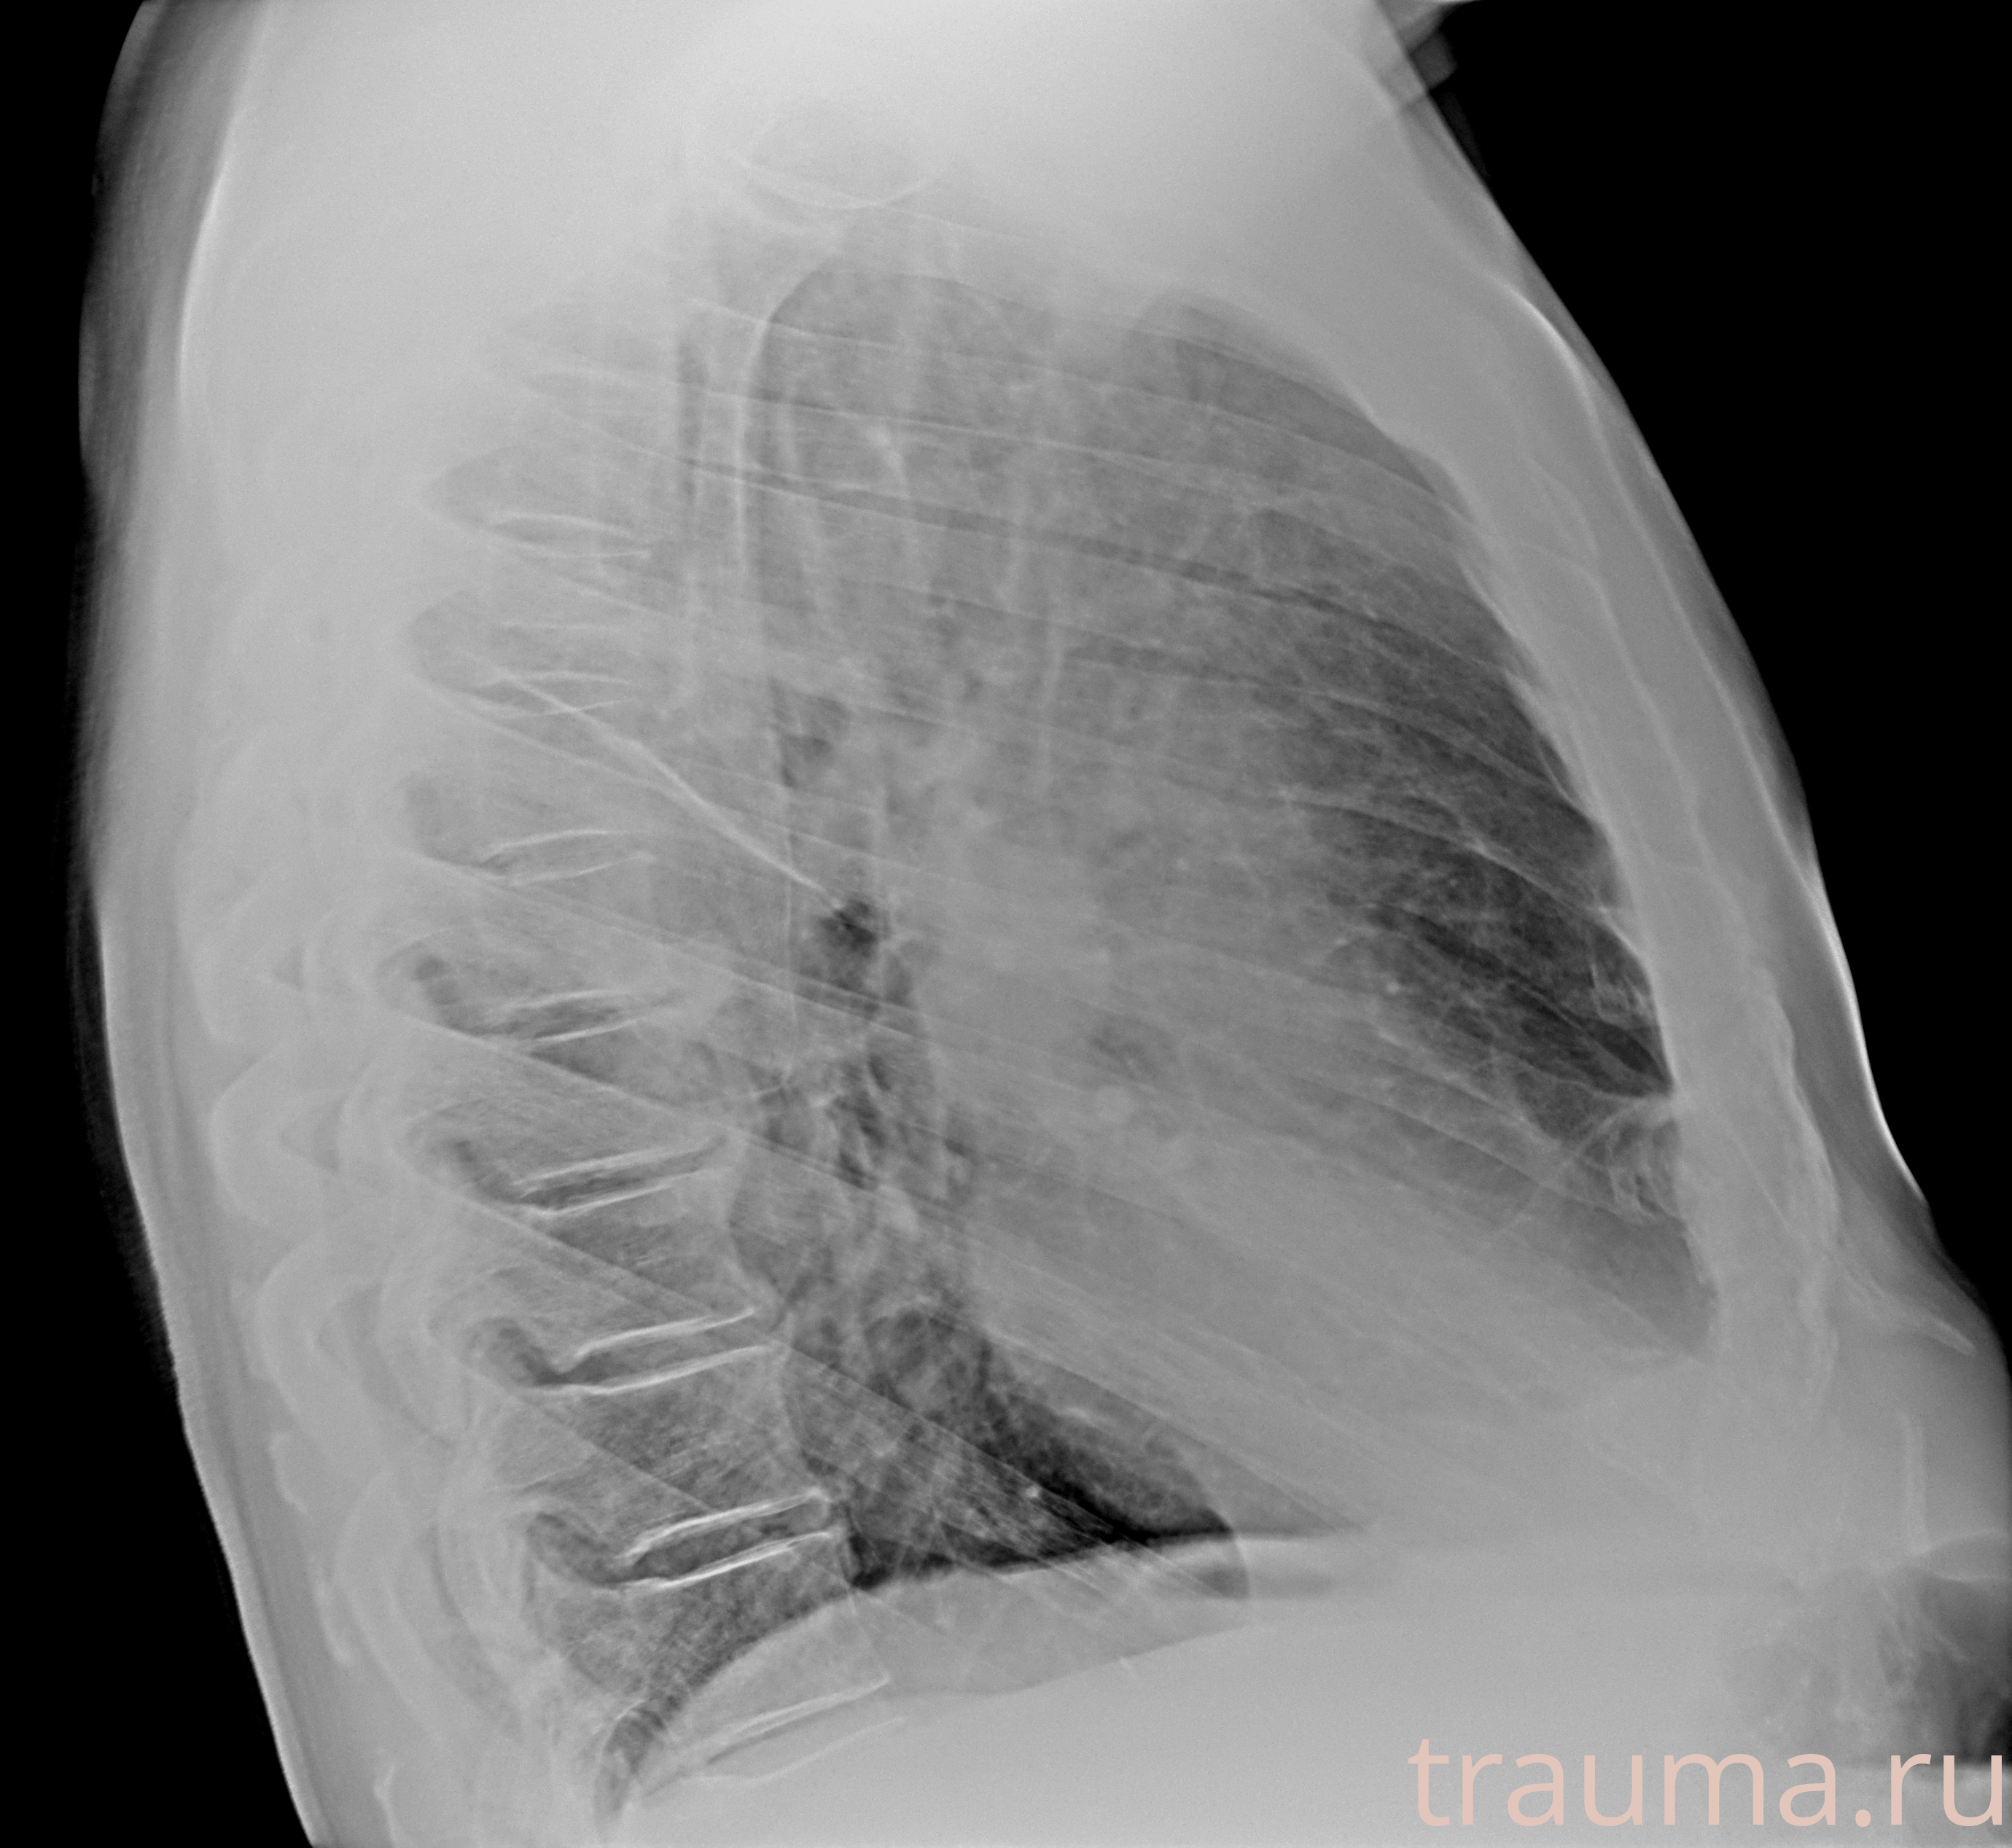

Рентгенограммы

Рентген на дому: по вашему адресу приезжает врач-рентгенолог, травматолог-ортопед с мобильным рентгеновским аппаратом, проводит диагностику травмы или заболевания, делает необходимые рентгенограммы, дает рекомендации по дальнейшему лечению. Получить качественные снимки в домашних условиях возможно благодаря уникальной методике, разработанной МосРентген Центром для института  Склифосовского